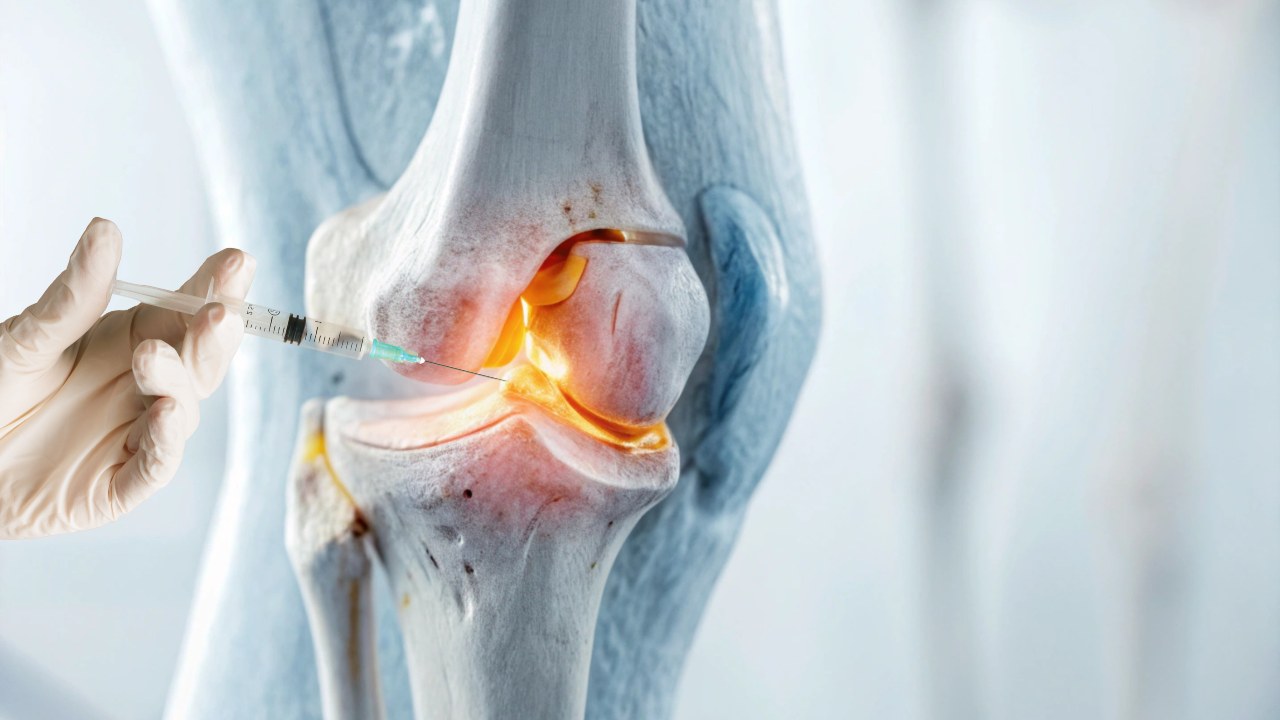

INFILTRAÇÃO ARTICULAR Agendar consulta A infiltração articular é um procedimento indicado para pacientes que sofrem com dores persistentes nas articulações e que não obtiveram bons